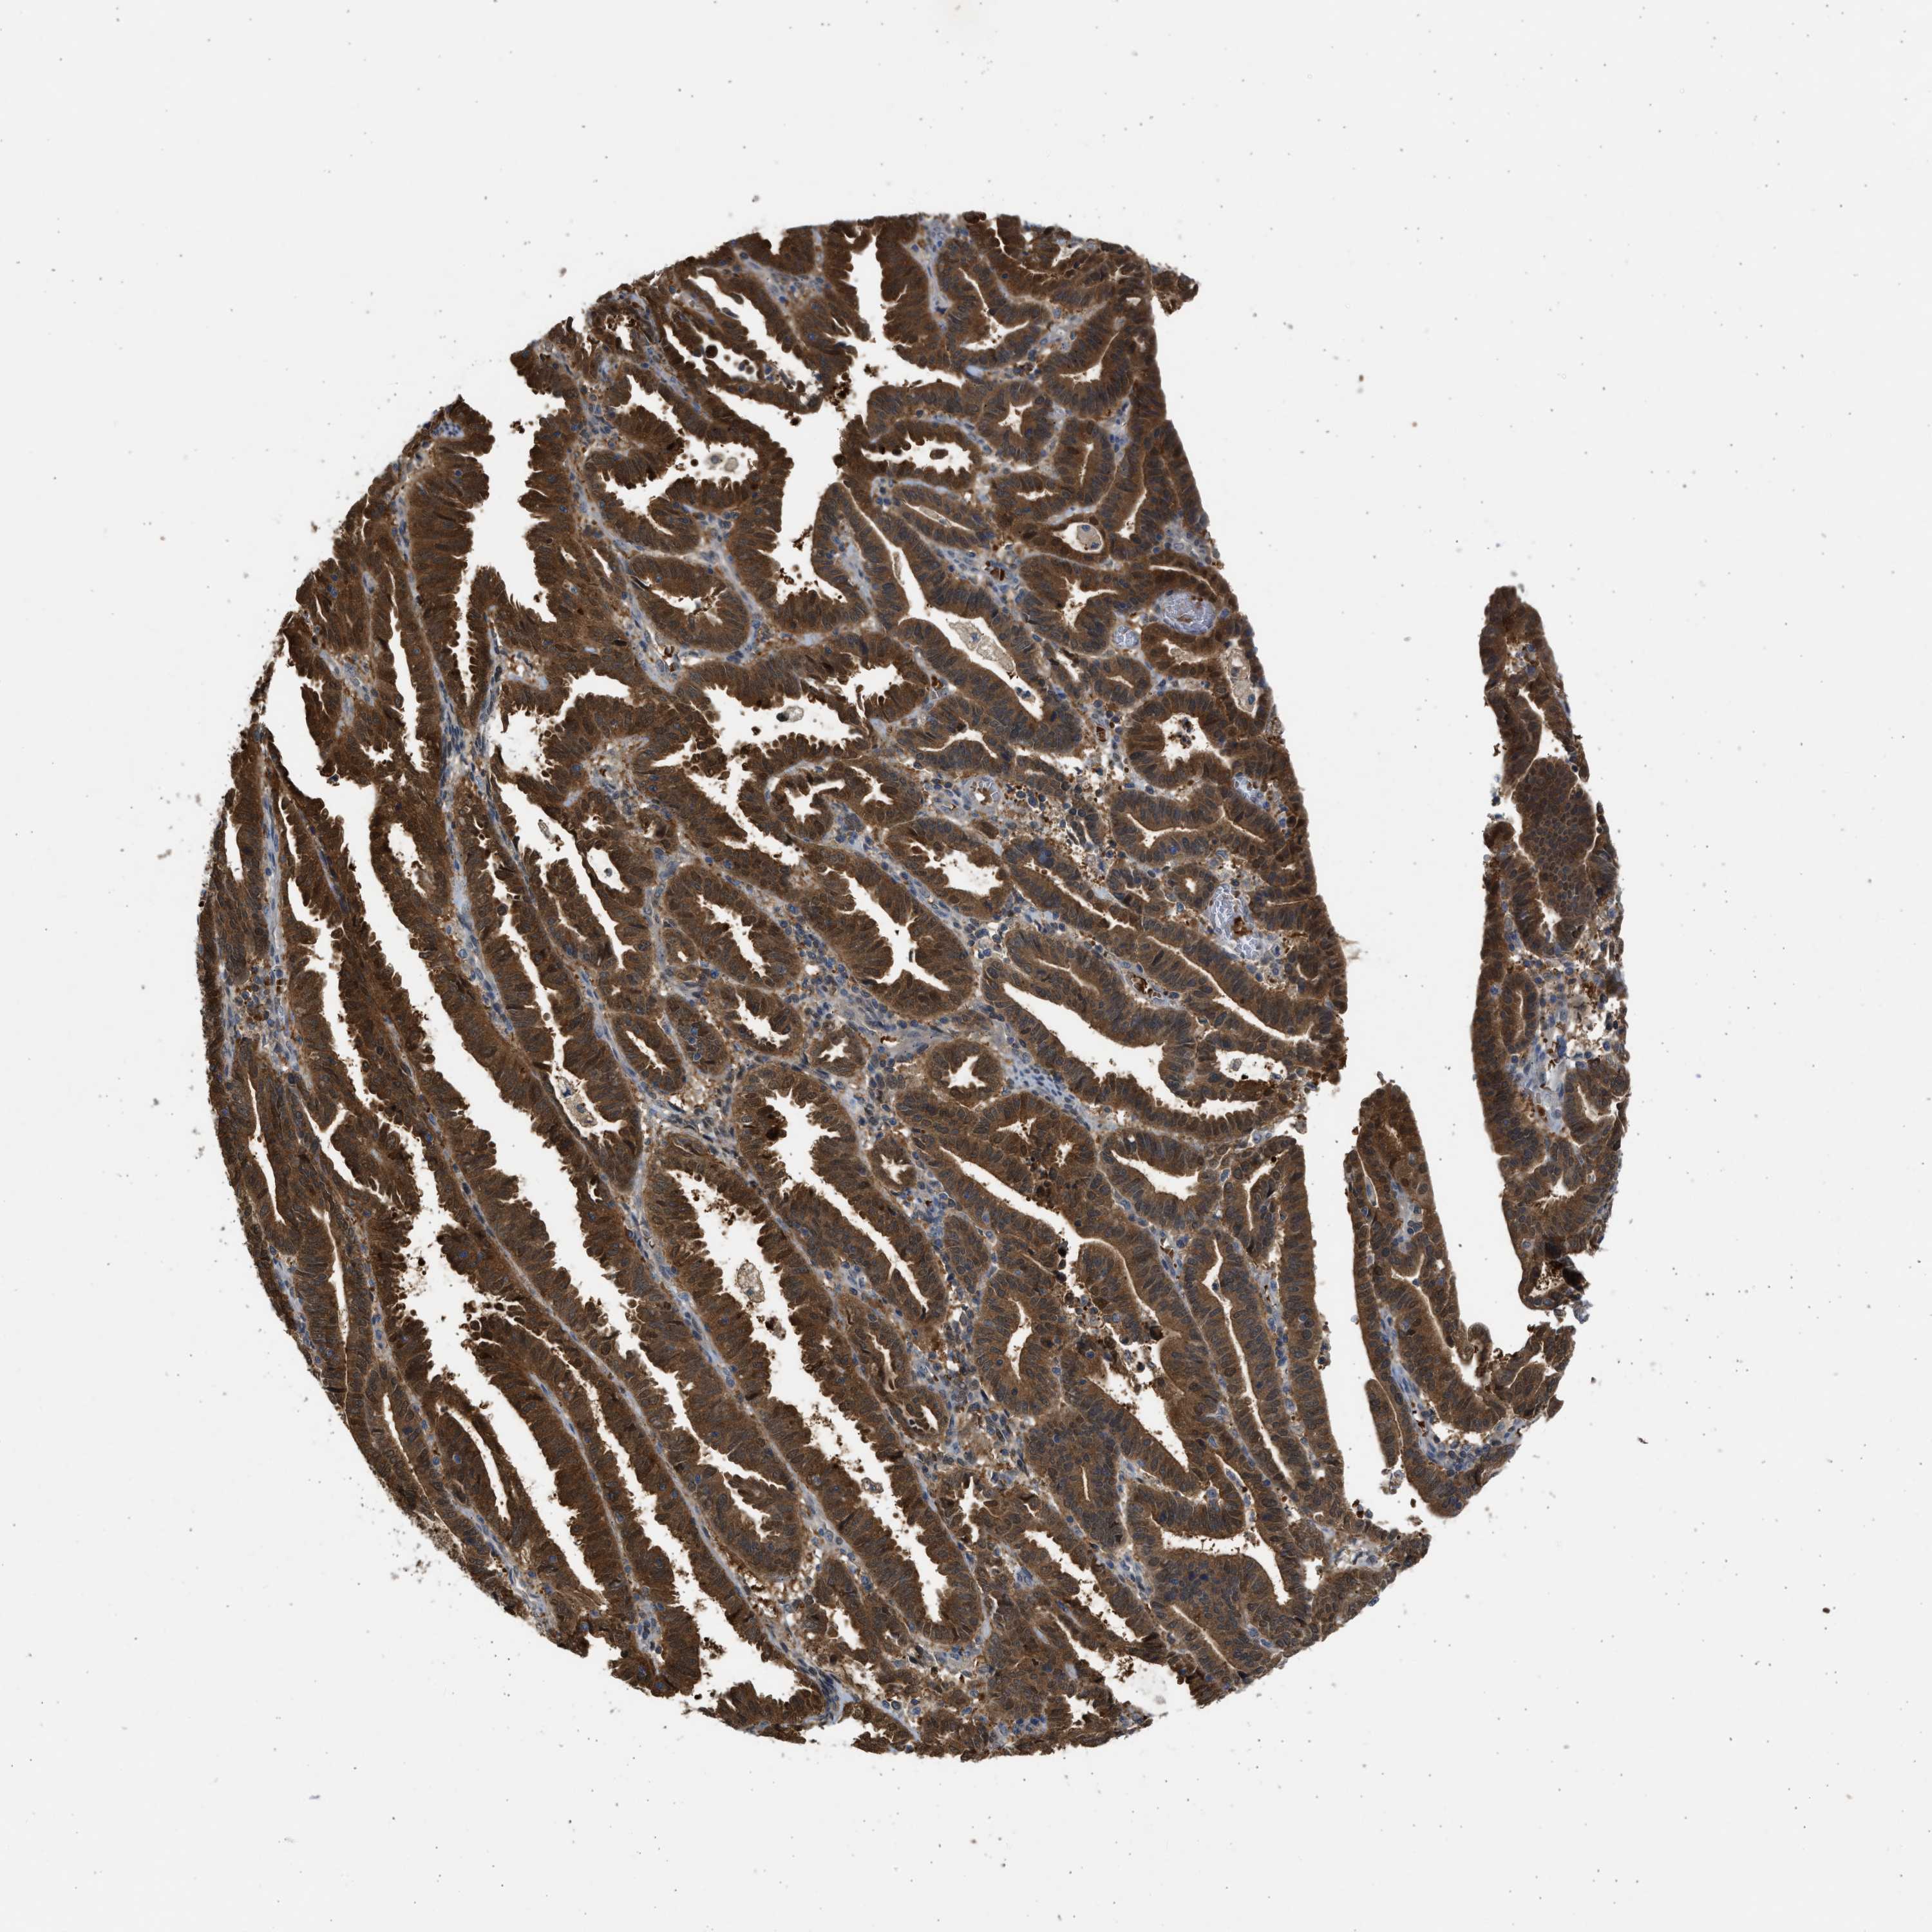

ENDOMETRIAL CANCER - Protein expressioni

A mouse-over function shows sample information and annotation data. Click on an image to view it in a full screen mode. Samples can be filtered based on level of antibody staining by selecting one or several of the following categories: high, medium, low and not detected. The assay and annotation is described here.

Note that samples used for immunohistochemistry by the Human Protein Atlas do not correspond to samples in the TCGA dataset.

Antibody stainingi

Antibody staining in the annotated cell types in the current human tissue is reported as not detected, low, medium, or high, based on conventional immunohistochemistry profiling in selected tissues. This score is based on the combination of the staining intensity and fraction of stained cells.

Each image is clickable and will lead to virtual microscopy that enables deeper exploration of all samples and also displays staining intensity scores, fraction scores and subcellular localization as well as patient and tissue information for each sample.

Antibody CAB018561

Staining

High

Medium

Low

Not detected

Intensity

Strong

Moderate

Weak

Negative

Quantity

>75%

75%-25%

<25%

None

Location

Nuclear

Cytoplasmic/membranous

Cytoplasmic/membranous,nuclear

Adenocarcinoma, NOS